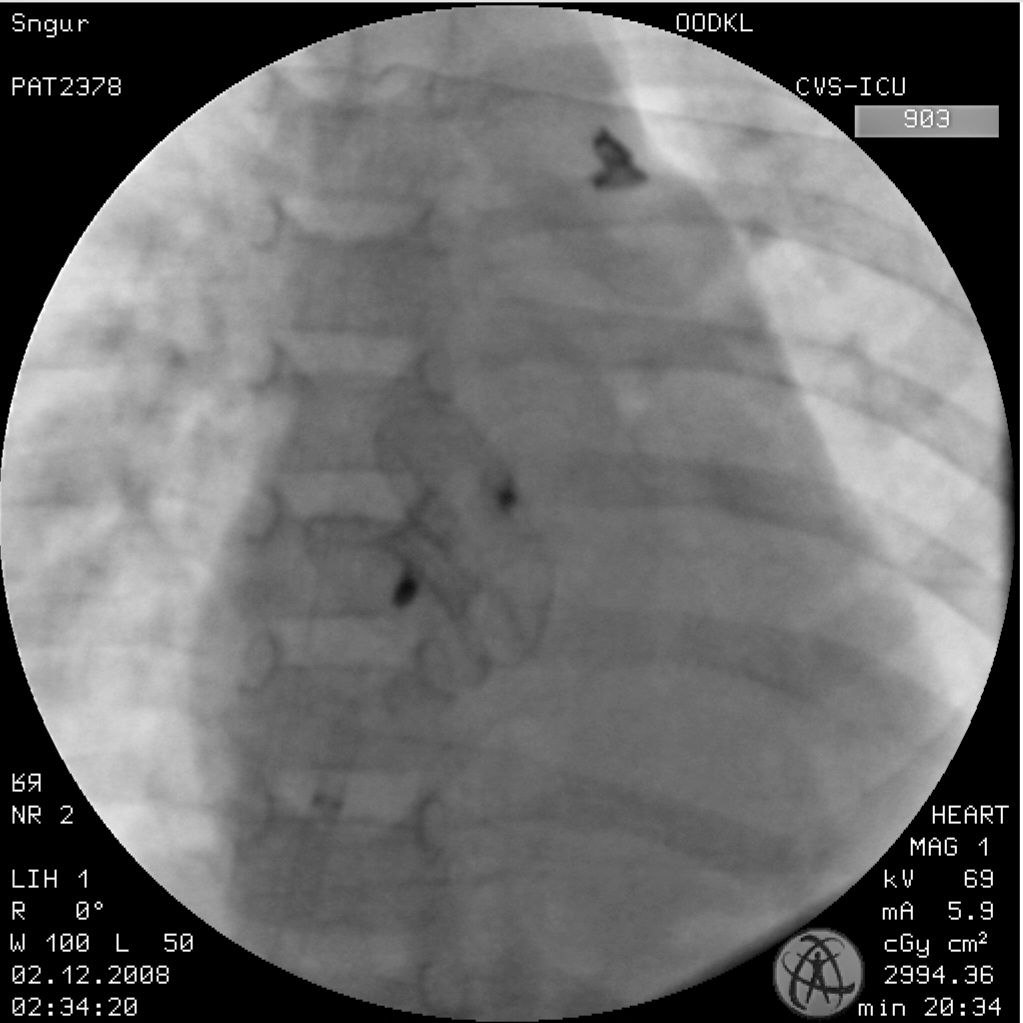

But Polya's heart needs help. A double hole measuring more than a centimetre prevents it from working properly.

"They did a follow-up ultrasound. The doctors say everything went very well. They told me that this is a very rare case. Not in terms of defects, but in terms of treatment. First, the holes are large, but they managed to close both defects at once through the femoral artery. Secondly, people are often deterred by the cost of this treatment, so it is often done in stages with a long interval between them. I have said it before, and now I want to shout it out loud — OUR PEOPLE ARE THE BEST. OUR DOCTORS ARE TRUE MASTERS OF THEIR CRAFT!"